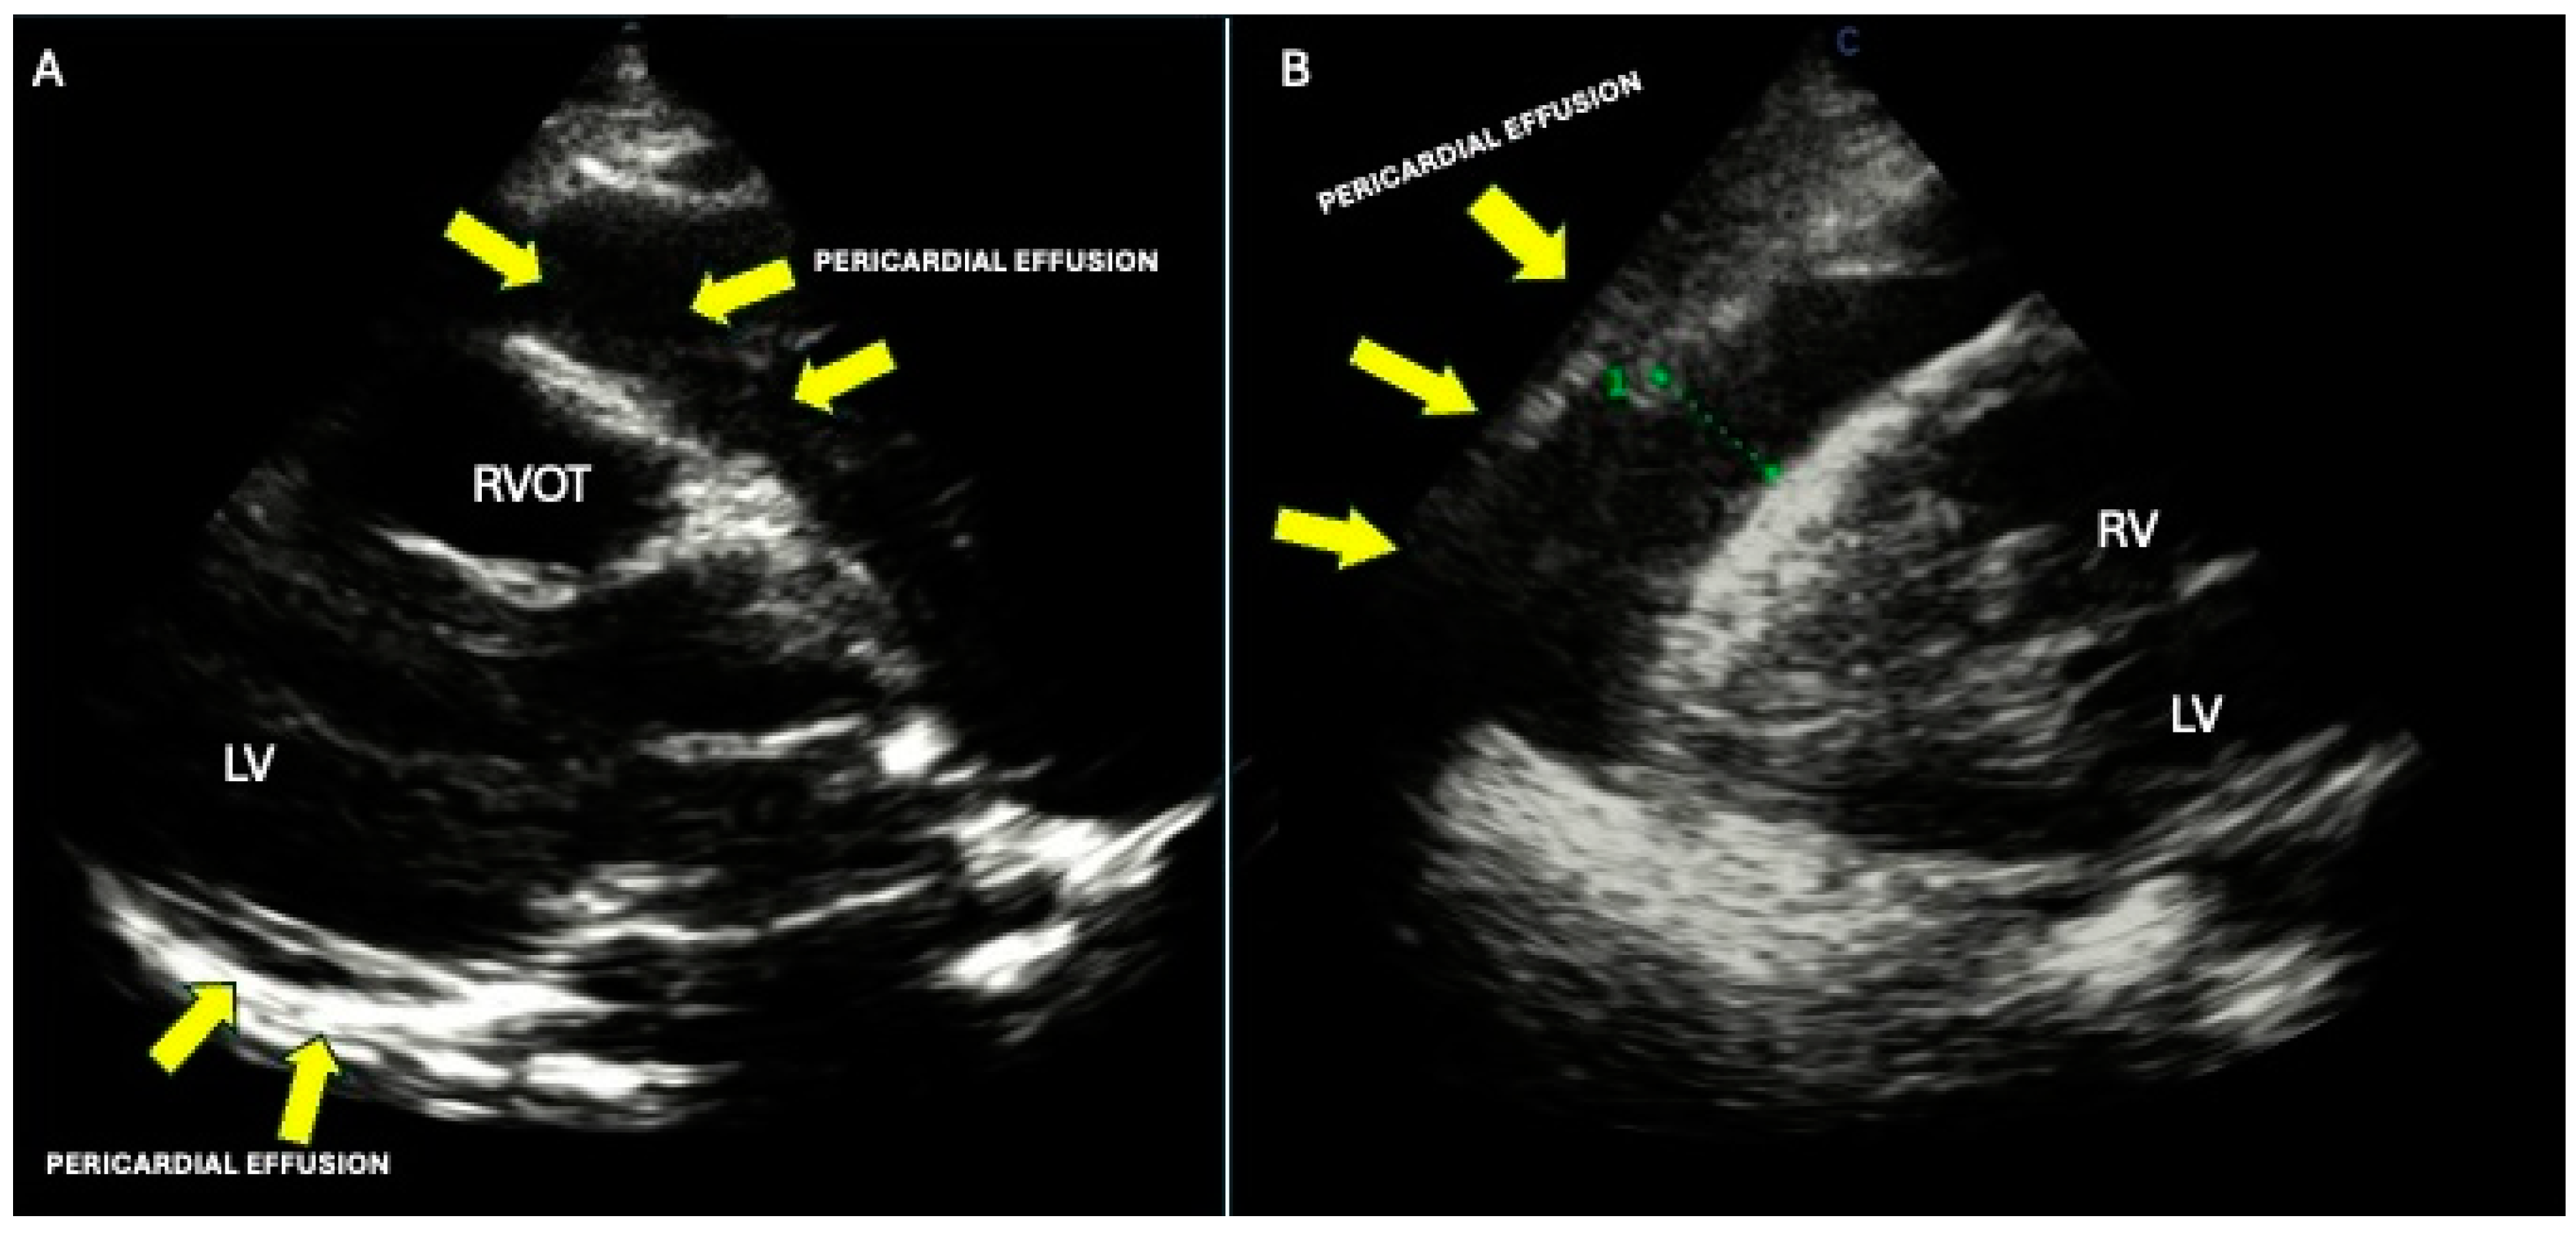

9. Pericardial Involvement

- Mori, S.; Bertamino, M.; Guerisoli, L.; Stratoti, S.; Canale, C.; Spallarossa, P.; Porto, I.; Ameri, P. Pericardial effusion in oncological patients: Current knowledge and principles of management. Cardio-Oncology 2024, 10, 8. (In English) [Google Scholar] [CrossRef] [PubMed]

- Adler, Y.; Charron, P.; Imazio, M.; Badano, L.; Barón-Esquivias, G.; Bogaert, J.; Brucato, A.; Gueret, P.; Klingel, K.; Lionis, C.; et al. 2015 ESC Guidelines for the diagnosis and management of pericardial diseases. Eur. Heart J. 2015, 36, 2921–2964. (In English) [Google Scholar] [CrossRef] [PubMed]

- L’Angiocola, P.; Donati, R. Cardiac masses in echocardiography: A pragmatic review. J. Cardiovasc. Echography 2020, 30, 5–14. (In English) [Google Scholar] [CrossRef]

- Aggeli, C.; Dimitroglou, Y.; Raftopoulos, L.; Sarri, G.; Mavrogeni, S.; Wong, J.; Tsiamis, E.; Tsioufis, C. Cardiac Masses: The Role of Cardiovascular Imaging in the Differential Diagnosis. Diagnostics 2020, 10, 1088. (In English) [Google Scholar] [CrossRef] [PubMed]